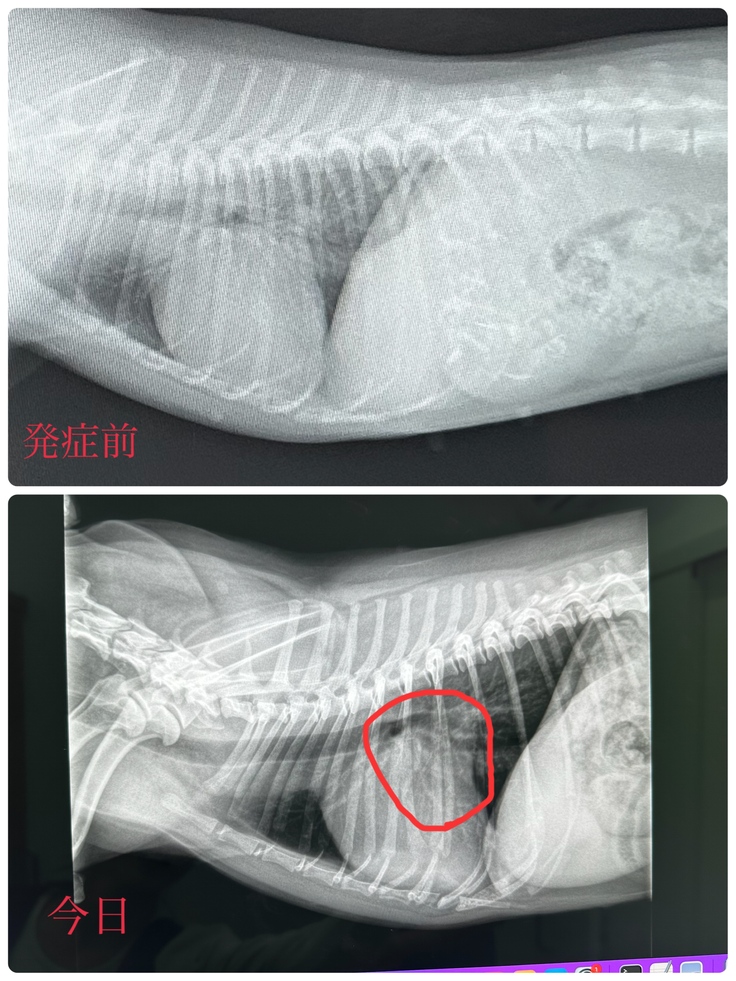

昨年10月より利尿剤の量が増え、そこから状態が安定していて、11月にレントゲンを撮って以来久々のレントゲンでした!(エコーは毎月行ってました🙌)結果、利尿剤が効いてくれているおかげで、心臓が少し小さくなってくれてました😣✨

でも今は状態が安定していても、手術をしない限りいつ悪化するか分からず、クレアはもう余命1年もありません😭2024年年を越せないかもしれません...左心房が小さくなったとはいえ、発症前の心臓と比べるとかなり大きくなっています😣